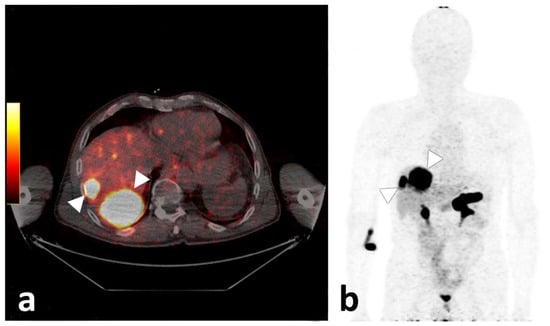

Figure 5. Axial fused PET/CT image of participant 3, demonstrating two liver metastases with high tracer uptake (a). On the (b), the corresponding maximum intensity projection is given, also demonstrating strong physiologic pancreatic as well as rectal and diffuse small bowel tracer accumulation.

Even though physiological 68Ga-NeoBOMB1 organ distribution was uniform in all participants with strong uptake mainly in the pancreas and urinary system [25], tumor uptake varied. Tracer accumulation in all lesions was shown in 33.3% (n = 3) of participants: 33.3% (n = 3) showed tracer accumulation only in a subset of lesions; and 33.3% (n = 3) showed no increased uptake in tumor lesions identified on CT (please also refer to the illustrative Figure 5). In three participants, a mixed uptake—i.e., a subset of lesions with no tracer uptake in the presence of other lesions with tracer uptake—were observed (Figure 6). On a per-lesion basis, 17 of 37 lesions (45.9%) were detected by 68Ga-NeoBOMB1, whereas 16 lesions (54.1%) were negative on 68Ga-NeoBOMB1 PET, explained in part by a significantly lower tracer uptake in lesions with necrotic CT appearance. On the other hand, five lesions (13.5%) could only be identified via 68Ga-NeoBOMB1-PET and were not initially evident on CT. Although the current gold standard for staging GIST is still contrast-based CT including Choi-criteria to report on vitality [26], the decision was made early on to include all GIST lesions found with either CT, 68Ga-NeoBOMB1-PET, or a combination of both methods to define the overall disease burden most accurately. Overall, we could corroborate study findings by Dimitrakopoulou-Strauss et al. in patients with GIST using 68Ga-BZH3, that also showed variable uptake in only seven out of 17 patients and eight out of 30 lesions [14].